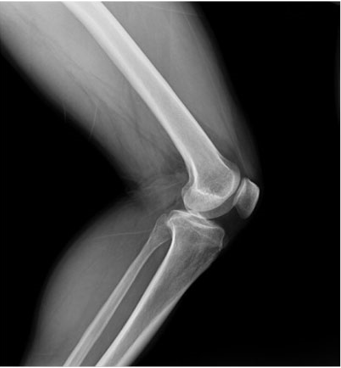

臨床圖片

微信圖片_20210927001109